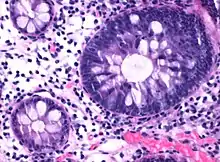

| Tubulovillous adenoma (tubular component – left of image, villous component – right of image). H&E stain. | |

Tubulovillous adenoma

Tubulovillous adenoma, TVA are considered to have a higher risk of becoming malignant (cancerous) than tubular adenomas.[9]